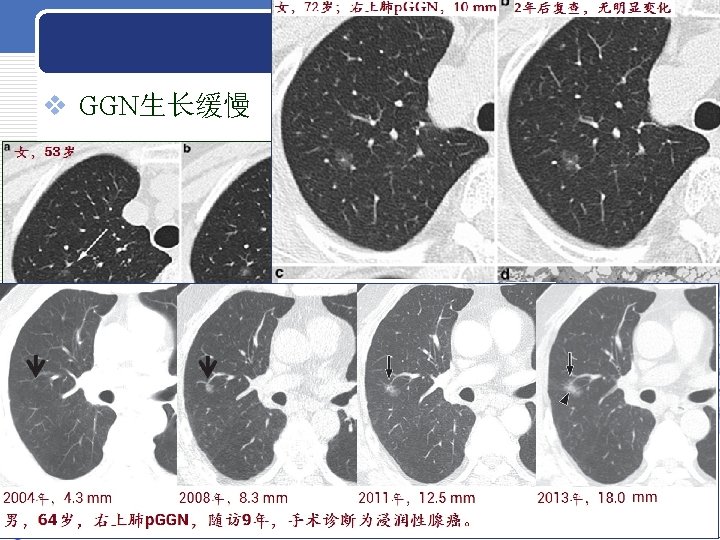

LUNG NODULE LUNG NODULE AAH p GGN 5